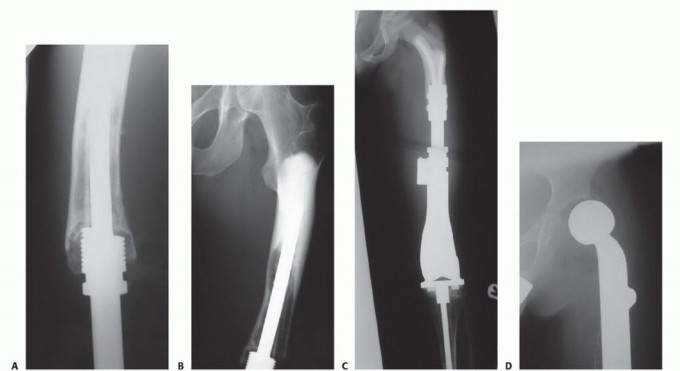

تُعد الأطراف الصناعية القابلة للتمدد (Expandable Prostheses) إنجازًا هندسيًا وطبيًا يغير قواعد اللعبة في علاج أورام العظام لدى الأطفال. هذه الأطراف مصممة خصيصًا لتعويض الجزء المفقود من العظم بعد استئصال الورم، مع ميزة فريدة وهي القدرة على التكيف مع نمو الطفل.

مفهوم الأطراف الصناعية القابلة للتمدد

بعد إزالة جزء من العظم الطويل المصاب بالورم، يتم زرع طرف صناعي داخلي (Endoprosthesis) ليحل محل العظم المفقود والمفصل المتضرر (مثل مفصل الركبة أو الكتف أو الفخذ). الفرق الجوهري في هذه الأطراف للأطفال هو أنها تحتوي على آلية تسمح بتمديدها تدريجيًا بمرور الوقت. هذا التمديد يعوض الفارق في الطول الذي يحدث مع نمو العظام الطبيعية الأخرى للطفل، مما يضمن بقاء الطرفين متساويين في الطول قدر الإمكان.

الأطراف الصناعية القابلة للتمدد تحل هذه المشكلة بشكل مباشر، حيث تسمح للجراح بتعديل طول الطرف الصناعي بشكل دوري ليتناسب مع نمو الطفل، مما يوفر له فرصة لحياة أكثر طبيعية ونشاطًا.

آليات التمدد المختلفة

تطورت آليات تمديد الأطراف الصناعية بشكل كبير على مر السنين:

- الأطراف الميكانيكية القابلة للتمدد (Mechanically Expandable Prostheses):

- كانت هذه هي التقنية الأولية.

- تتطلب جراحة بسيطة كلما احتاج الطرف للتمديد. يقوم الجراح بإجراء شق صغير، ثم يستخدم أداة خاصة لتمديد الطرف الصناعي ميكانيكيًا.

- على الرغم من فعاليتها، إلا أنها تتطلب تخديرًا وجراحة متكررة، مما يزيد من خطر العدوى والمضاعفات.

- الأطراف المغناطيسية القابلة للتمدد (Magnetically Expandable Prostheses):

- تمثل هذه التقنية أحدث الابتكارات وأكثرها شيوعًا حاليًا.